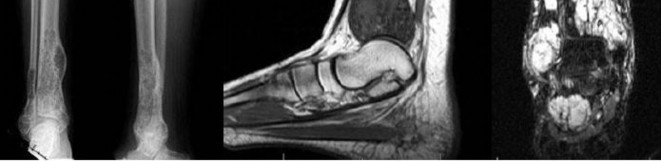

Question 17

A 35-year-old female is diagnosed with a locally aggressive giant cell tumor of the distal radius. Preoperative administration of Denosumab is planned to facilitate downstaging and joint-salvage surgery. What is the exact mechanism of action of Denosumab in this context?

Explanation

Denosumab is a fully human monoclonal antibody that specifically binds to RANKL (Receptor Activator of Nuclear factor Kappa-B Ligand). By binding to RANKL, it prevents it from interacting with the RANK receptor on the surface of osteoclasts and osteoclast precursors. In Giant Cell Tumor of bone, the neoplastic mononuclear stromal cells express high levels of RANKL, which aggressively recruits and activates the reactive multinucleated giant cells (osteoclasts) that cause bone destruction.